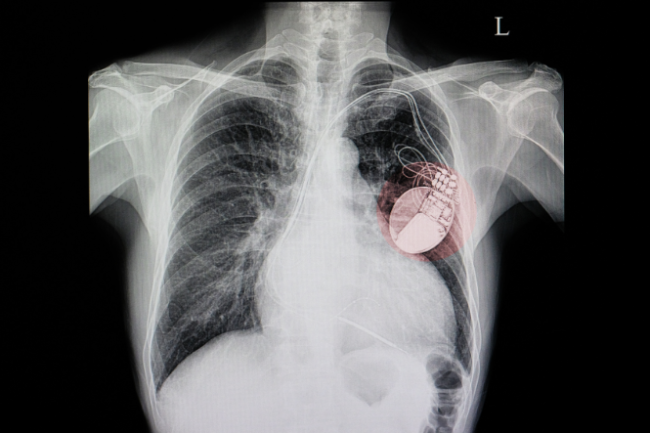

Pacemaker | Pūrere whakakapa manawa

Pacemaker

- A pacemaker (pūrere whakakapa manawa) is a small device designed to help your heart beat regularly.

- It contains a long-lasting battery and an electronic circuit sealed in a metal case.

- The pacemaker sits under your skin and produces an electrical impulse, which is sent directly to the heart muscle by one or two leads.

- When the impulse reaches the heart muscle, it causes the heart to beat.

The pacemaker leads are inserted into a vein below your collarbone and passed along this vein into your heart. The leads are then attached to the inside of the heart wall. The leads are tested and connected to the pacemaker. The pacemaker is then implanted under your skin, below your left or right shoulder. The procedure normally takes about one hour, although this can vary.

Image credit: Canva